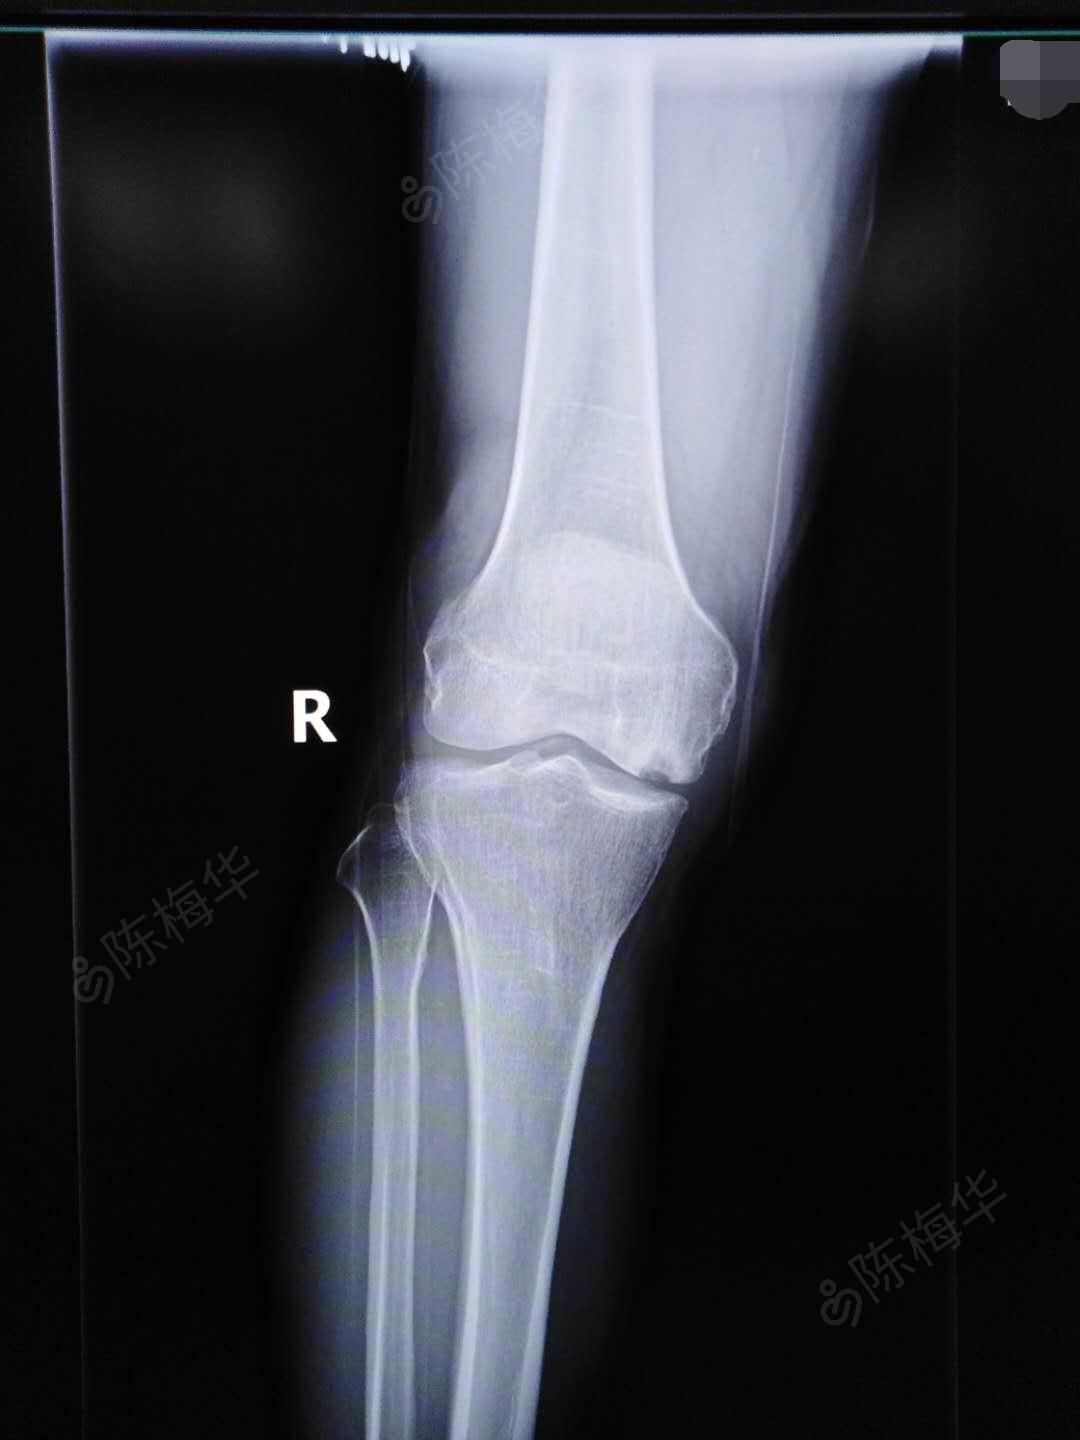

右胫骨内,外侧缘轻压痛,右膝关节被动活动正常,主动活动0度-110度,下

沙发回复江中浪花2011-07-14 00:43:04现附上附上左侧膝关节dr正侧位